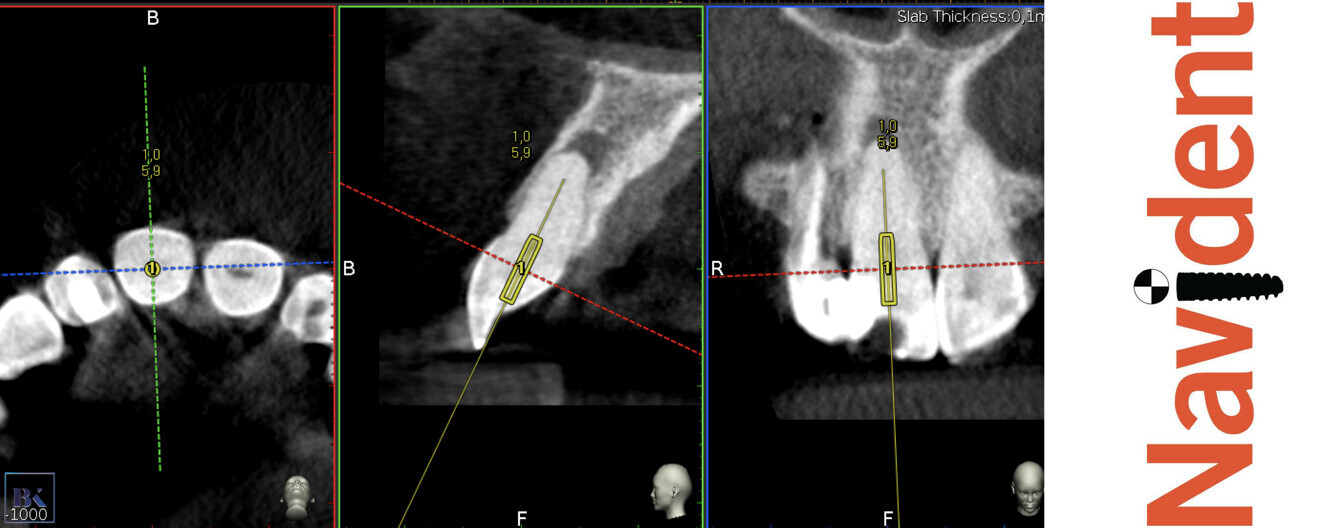

The access cavity was performed with the EndoGuide bur with the aid of the software. After reaching the depth of drilling on the prepared guide, another CBCT scan was performed to check the accuracy of the access cavity (Fig. 18). The CBCT scan revealed that the angulation of the access cavity was suitable but that the depth was insufficient. The EndoGuide drill and Navident were used one more time to reshape the access cavity. After gaining patency in the canal, the #10 K-file was used to establish the working length. The canal in the right incisor was shaped with Endostar E3 Azure up to size 40/0.04, and the canal in the left incisor was shaped up to size 45/0.04. In both canals, the irrigation protocol was performed with 5.25% sodium hypochlorite and 40.0% citric acid. Both solutions were activated with Eddy sonic tips, and sodium hypochlorite was additionally activated with Elements Free for intra-canal heating. The canals were dried with paper points (Fig. 19) and obturated with warm gutta-percha using the continuous wave technique, and a control radiograph was performed (Fig. 20). Finally, the composite sealing was performed and the occlusal check was done (Fig. 21).

Figs. 18a & b: CBCT check, sagittal plane. The axis of the access cavity was visible for both teeth.